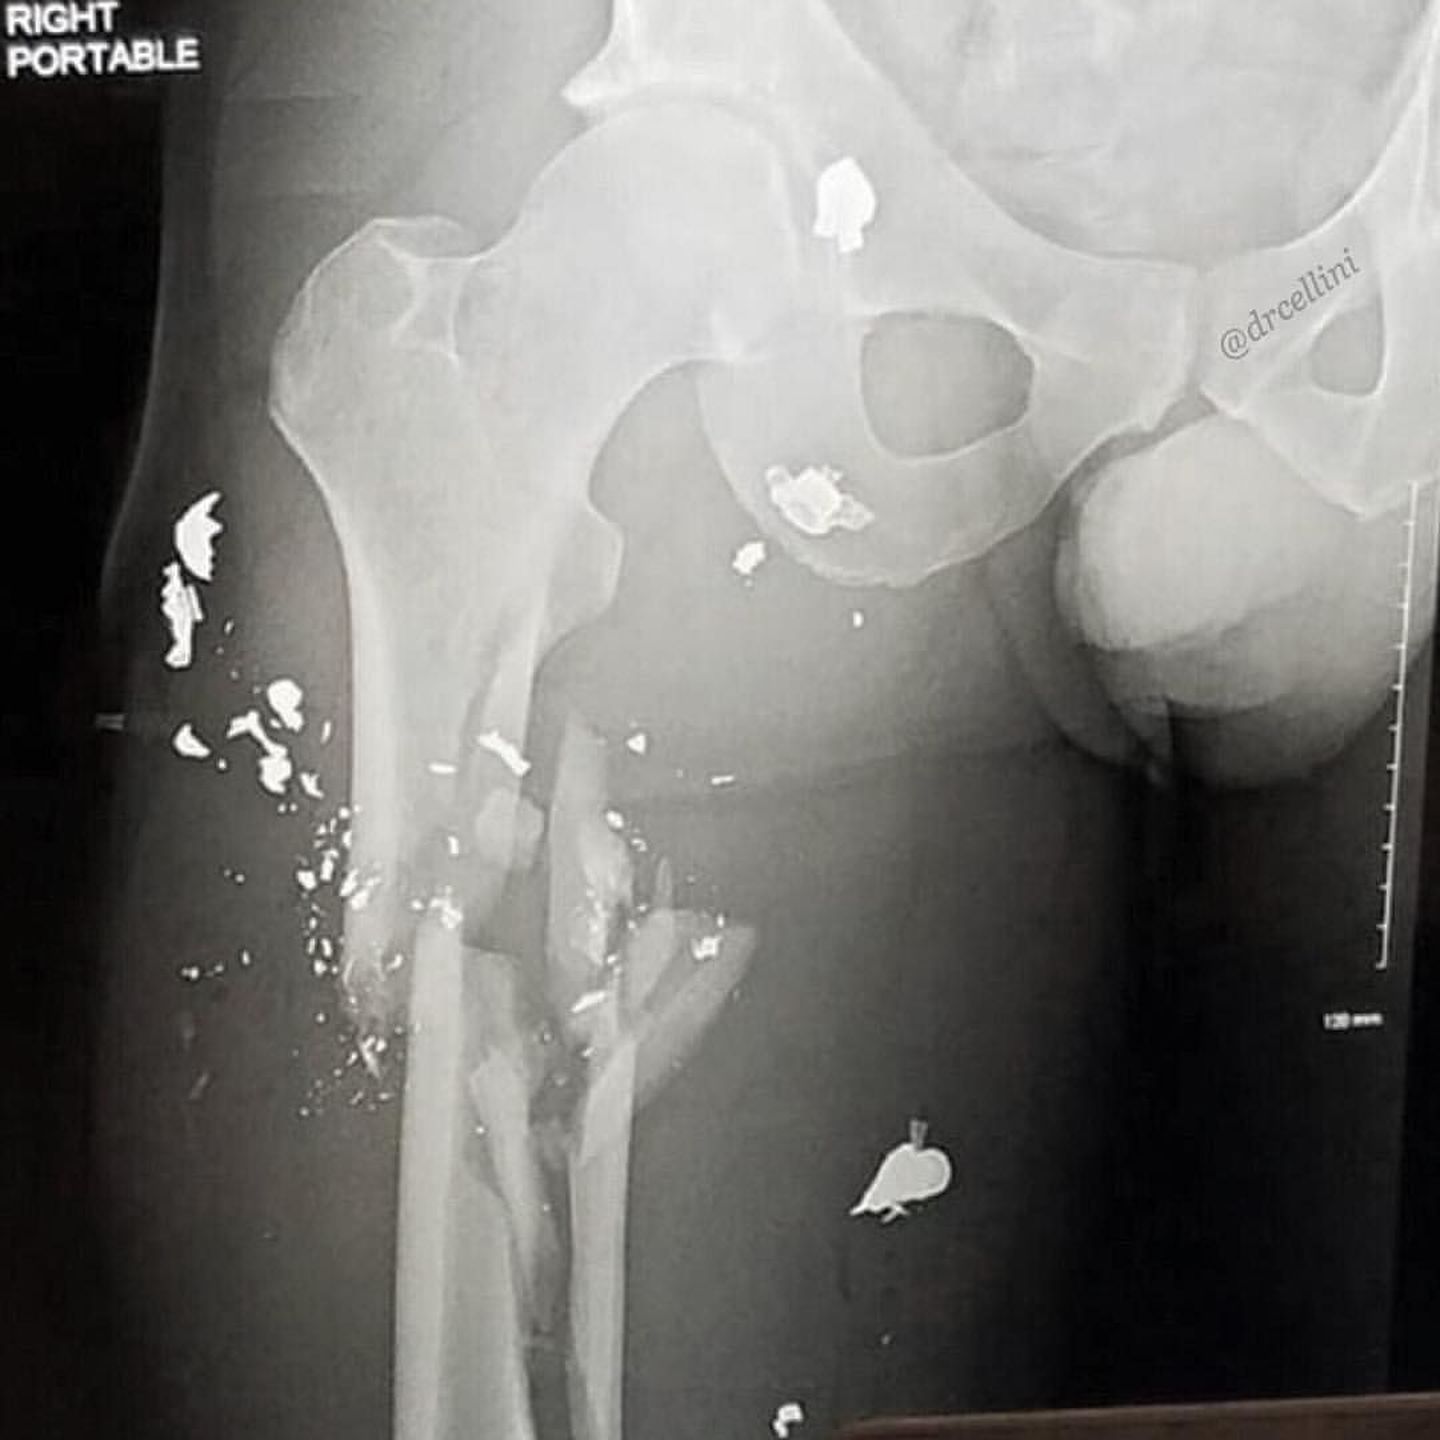

This is the kind of damage an AK-47 can cause. This patient was shot in the right leg by an AK-47 assault rifle at close range. It looks as if the bullet(s) directly hit the proximal femur, shattering it in the process, spreading ballistic fragments throughout the soft-tissues of the thigh. This kind of damage will warrant a trip to the OR for an intramedullary rod for fracture fixation. Photo by @drcellini